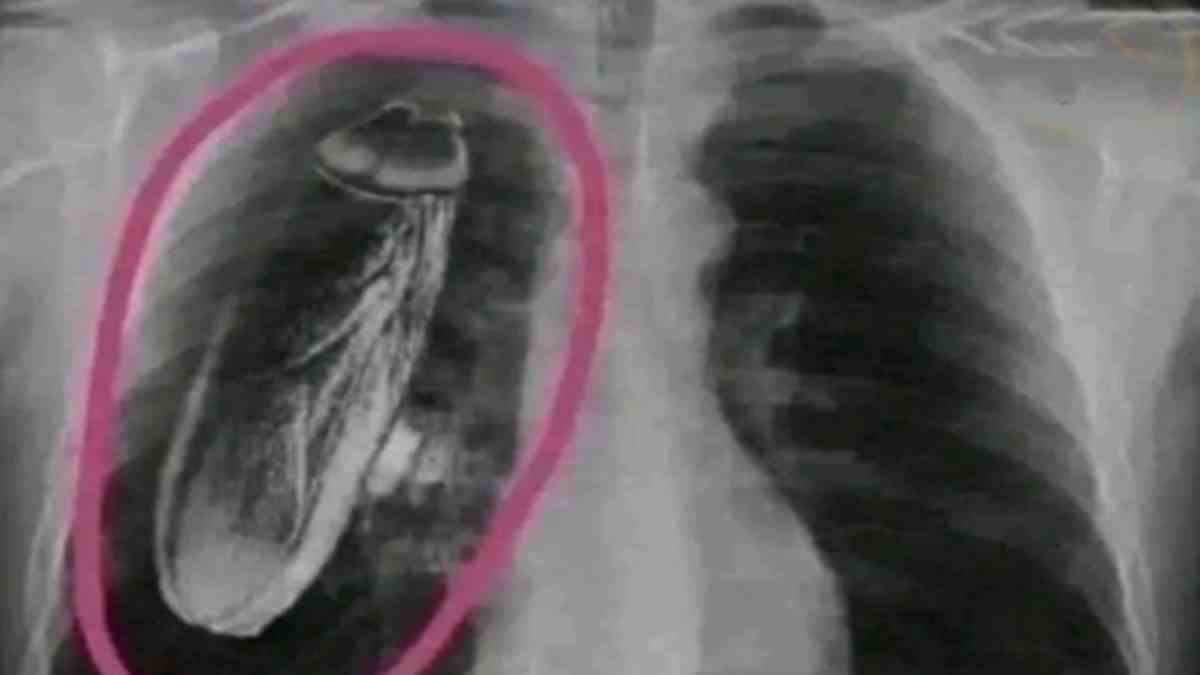

వైద్యుల నిర్లక్ష్యానికి ఈ ఘటన నిదర్శనం. తరచూ గుండె నొప్పి వస్తుందని ఓ పెద్దాయన ఆస్పత్రికి వెళితే.. ఎక్స్ రే తీసిన వైద్యులు ఆయన గుండెలో ప్రాణాలతో వున్న బొద్దింక వుందని షాకిచ్చారు. వైద్యం కోసం అమెరికా వెళ్లమన్నారు. అయితే అసలు విషయం తెలుసుకుని ఆ పెద్దాయన షాక్ అయ్యాడు.

వివరాల్లోకి వెళితే.. ఒక వృద్ధుడికి పదే పదే ఛాతీ నొప్పి వచ్చిన తర్వాత ఒక వింత సంఘటన బయటపడింది. అతను ప్రభుత్వ ఆసుపత్రికి వెళ్లి చెకప్ చేయించుకున్నప్పుడు అతని ఎక్స్ రే రిపోర్ట్ గురించి దిగ్భ్రాంతికరమైన వివరణ వచ్చింది. అతని గుండెలో బతికి ఉన్న బొద్దింక ఉందని ఆసుపత్రి సిబ్బంది అతనికి చెప్పారు.

శస్త్రచికిత్స కోసం అమెరికాకు వెళ్లాలని వారు సలహా ఇచ్చారు. వృద్ధుడు వారిని నమ్మి అమెరికాకు చేరుకోవడానికి పెద్ద మొత్తంలో డబ్బు ఖర్చు చేశాడు. అక్కడికి చేరుకున్న తర్వాత, వైద్యులు కొత్త స్కాన్లు, పరీక్షలు నిర్వహించారు. అతని గుండెలో బొద్దింక లేదని వారు నిర్ధారించారు.

సమస్య ప్రభుత్వ ఆసుపత్రిలోని ఎక్స్ రే యంత్రంతో సంబంధం కలిగి ఉంది. ఈ కేసు తీవ్రమైన ప్రశ్నలను లేవనెత్తుతుంది. బతికి ఉన్న బొద్దింక గుండెలో బతికే ఉంటుందని అతను ఎలా నమ్మాడు? శస్త్రచికిత్స కోసం వేరే దేశానికి వెళ్లే ముందు అతను రెండవ అభిప్రాయం ఎందుకు తీసుకోలేదు? అతని కుటుంబం పాత్ర కూడా అస్పష్టంగా ఉంది. అతని వద్ద అమెరికాకు వెళ్లడానికి తగినంత డబ్బు ఉంటే, అతని ఇంట్లో ఎవరైనా విద్యావంతులు కావాలి.